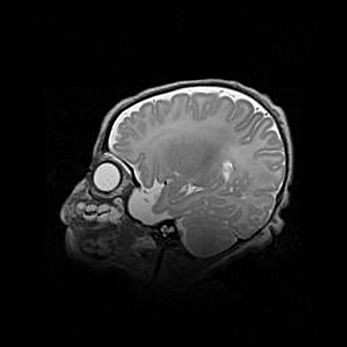

Аномалия Денди-Уокера. Признаки гипоплазии мозолистого тела.

Возраст: 5 месяцев 3 дня

Вес: 5550 г

Пол: мужской

Окружность головы: 39 см

Срок гестации: 40 недель

Аномалия Денди-Уокера – это порок развития головного мозга, для которого характерна триада симптомов: гипотрофия или аплазия червя мозжечка и/или полушарий мозжечка, расширение четвёртого желудочка с формированием ликворной кисты задней черепной ямки, гипертензионная гидроцефалия различной степени.

Гипоплазия мозолистого тела относится к дефектам внутриутробного этапа развития мозговой ткани, возникающим в процессе закладки структур головного мозга, что происходит на начальных этапах развития эмбриона.